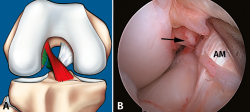

Figura 7. Rotura parcial del fascículo anteromedial (AM). A: esquema que ilustra una rotura parcial del ligamento cruzado anterior (LCA) afectando al fascículo AM; B: imagen artroscópica de la rodilla izquierda desde el portal anterolateral. Rotura completa del fascículo AM (flecha) con un fascículo posterolateral (PL) intacto y tenso a la exploración con el palpador.

Sin embargo, a pesar de estos esfuerzos, la valoración de la actitud terapéutica no se basa en los hallazgos de RM. Si bien la valoración combinada de la exploración clínica y los hallazgos de RM permite establecer una sospecha de inestabilidad en una lesión parcial del LCA, la exploración bajo anestesia con la maniobra de pivot shift sigue siendo el test más fiable en la valoración funcional del LCA y el tratamiento quirúrgico definitivo se debe basar en la exploración artroscópica(17)(Figuras 7 y 8).

Figura 8. Rotura parcial del fascículo posterolateral (PL). A: esquema que ilustra una rotura parcial del ligamento cruzado anterior (LCA) afectando al fascículo PL; B: visión artroscópica de la rodilla derecha desde el portal anterolateral. Se observa una rotura completa del fascículo PL (flecha), tras la separación con el palpador del fascículo anteromedial (AM).